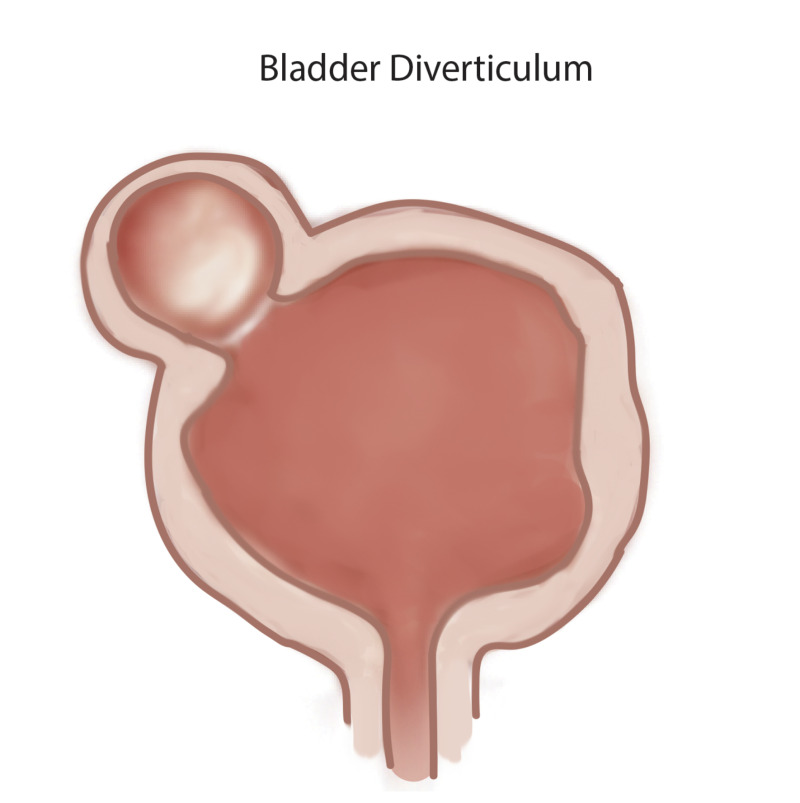

Bladder Diverticulum StatPearls NCBI Bookshelf